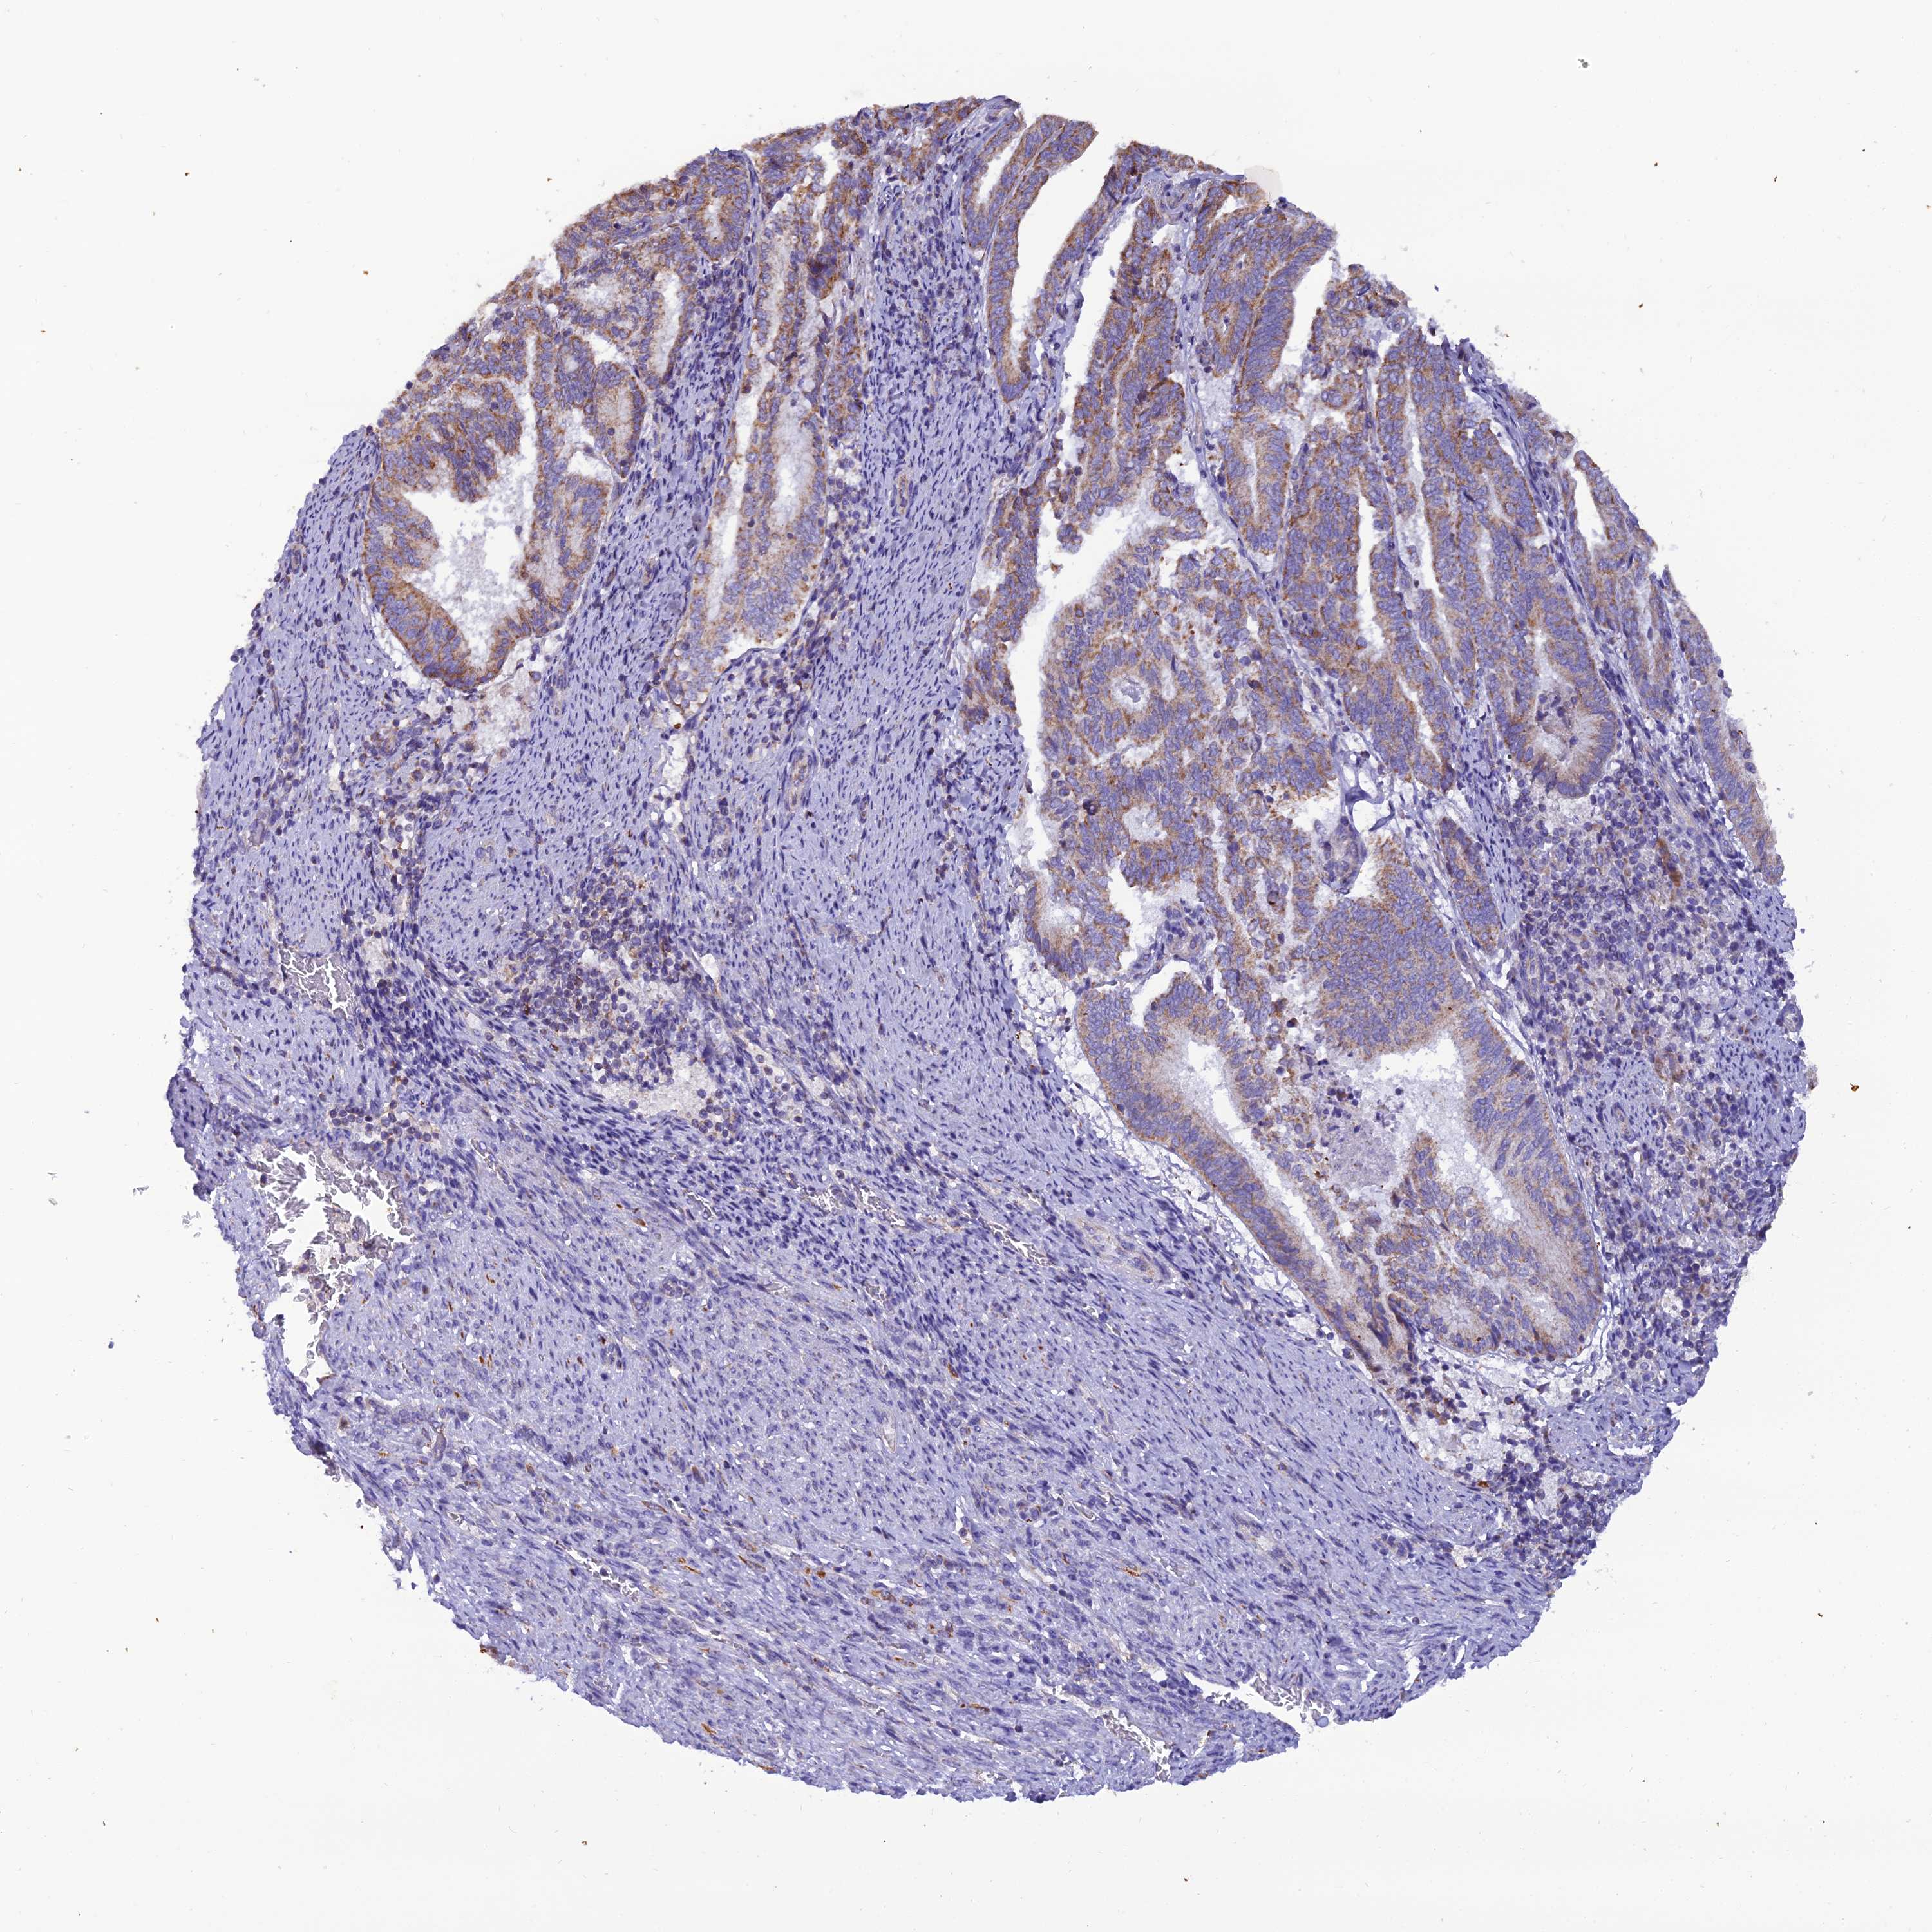

ENDOMETRIAL CANCER - Protein expressioni

A mouse-over function shows sample information and annotation data. Click on an image to view it in a full screen mode. Samples can be filtered based on level of antibody staining by selecting one or several of the following categories: high, medium, low and not detected. The assay and annotation is described here.

Note that samples used for immunohistochemistry by the Human Protein Atlas do not correspond to samples in the TCGA dataset.

Antibody stainingi

Antibody staining in the annotated cell types in the current human tissue is reported as not detected, low, medium, or high, based on conventional immunohistochemistry profiling in selected tissues. This score is based on the combination of the staining intensity and fraction of stained cells.

Each image is clickable and will lead to virtual microscopy that enables deeper exploration of all samples and also displays staining intensity scores, fraction scores and subcellular localization as well as patient and tissue information for each sample.

Antibody HPA044620

Antibody HPA058621

Staining

High

Medium

Low

Not detected

Intensity

Strong

Moderate

Weak

Negative

Quantity

>75%

75%-25%

<25%

None

Location

Nuclear

Cytoplasmic/membranous

Cytoplasmic/membranous,nuclear

Adenocarcinoma, NOS